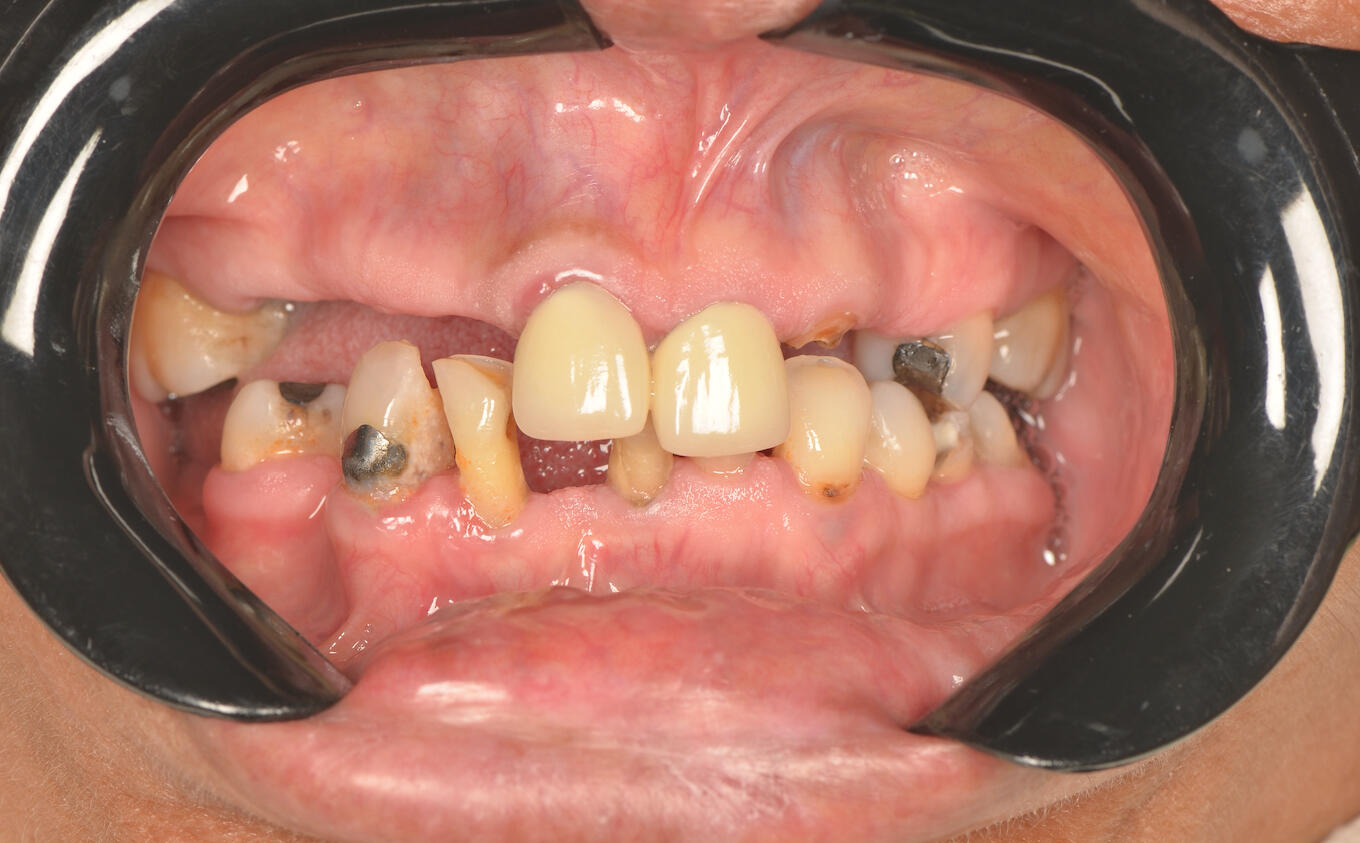

Complex Prosthetic Rehabilitation in an International Patient with Prosthetic Failure and Periodontal ComplicationsA patient from the state of Georgia (United States) sought specialized dental treatment due to complex failure of existing fixed dental prostheses. Clinical examination revealed prosthetic fractures, gingival inflammation, food impaction, compromised periodontal support tissues, and disruption of the smile line and occlusal harmony.A comprehensive prosthetic and periodontal treatment protocol was implemented, focusing on biological compatibility, functional occlusion, periodontal stabilization, and esthetic reintegration. Advanced restorative techniques and biomaterials were utilized to ensure long-term functional and biological stability.Post-treatment outcomes demonstrated improved periodontal health, occlusal function, and esthetic balance of the smile.This international case reflects transnational recognition of clinical expertise and highlights the importance of high-level interdisciplinary restorative and periodontal rehabilitation in complex prosthetic failures.